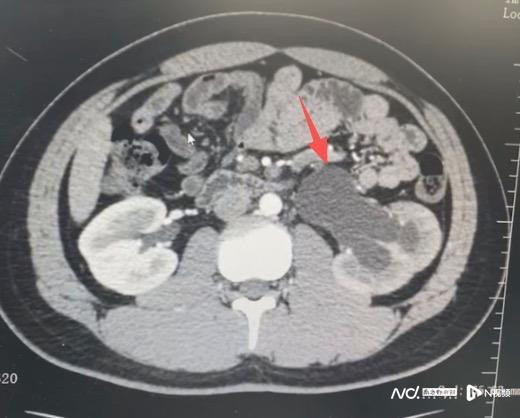

小宇本该在篮球场上挥洒汗水,却被出其不备的剧烈腰痛逼进了病院。在广州医科大学附属第五病院(简称“广医五院”)泌尿外科门诊,查验效果让家长后怕不已:导致小宇可怜的并非大致的肌肉拉伤,而是一个从降生就解除于今的先天性输尿管褊狭,他的肾脏已因此出现中度积水。

据广医五院泌尿外科徐桂彬主任先容,先天性输尿管褊狭是孩子降生时就存在的输尿管管谈褊狭问题。输尿管当作肾脏向膀胱运输尿液的“水管”,一朝发生褊狭,尿液就会像堵塞的河谈相同倒流回肾脏,导致肾积水。临床统计泄漏,这类疾病好发于男性患儿,且左侧更为多见。它最大的特色即是“早期无症状”,在轻度褊狭时,身段不会有任何不适。小宇的病情之是以解除了16年才被发现,恰是因为广阔穷乏针对性查验,直到肾脏被“撑”到极限,出现腰疼以至可能摸到包块时才就医。

所幸,由于发现还算实时,广医五院泌尿外科通过微创手术为其废除了顽固,保护了肾功能。徐桂彬主任暗示,要是小宇有进行如期体检,可能在降生1-2岁或者5岁时就能发现问题,况且不错更早进行手术料理。要是再晚一些发现,遥远的重度肾积水可能会导致肾功能不行逆的毁伤,以至肾衰退。